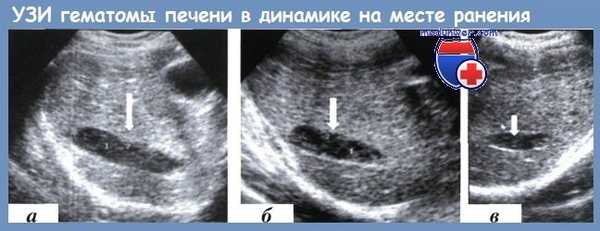

Данные УЗИ при гематоме печени в области раневого канала в динамике:

а — 3-й сутки после ранения; б — 7-е сутки; в — 17-е сутки

Незаменим метод УЗИ для контроля за изменениями структуры гематом паренхиматозных органов в области раневых каналов, в выявлении в этих зонах кровотока, что играет ключевую роль в предупреждении вторичного кровотечения в послеоперационном периоде.